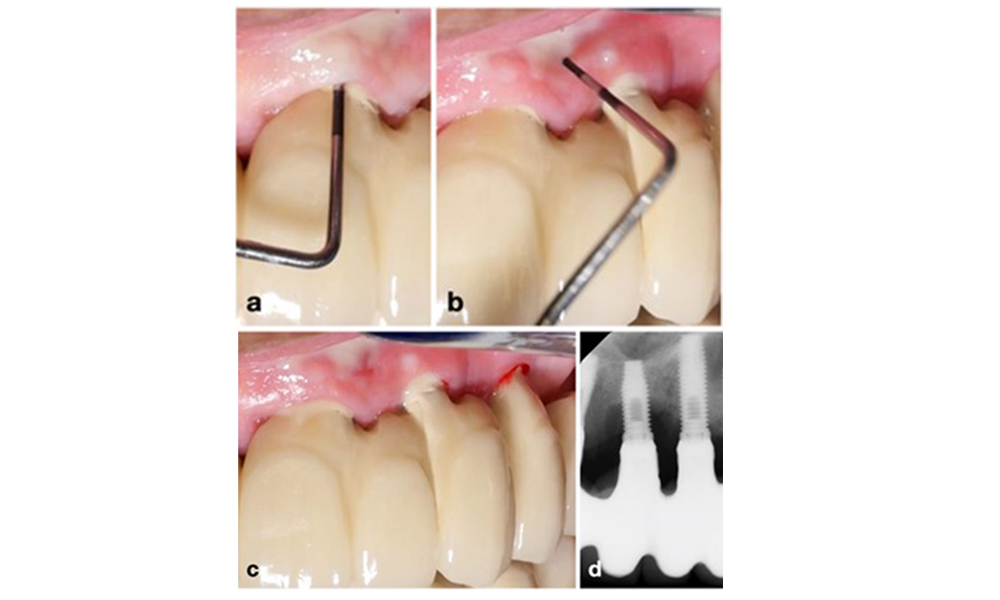

По време на Световния семинар за класификация на пародонталните и периимплантни заболявания и състояния през 2017 г. бяха определени диагностичните критерии за периимплантатен мукозит и периимплантит (Renvert et al. 2018). Периимплантният мукозит се дефинира като (1) наличие на възпаление около импланта (т.е. зачервяване, подуване, линия или капки кръв в рамките на 30 секунди от сондирането), но (2) без допълнителна костна загуба след първоначалното заздравяване (фигура 1 ).